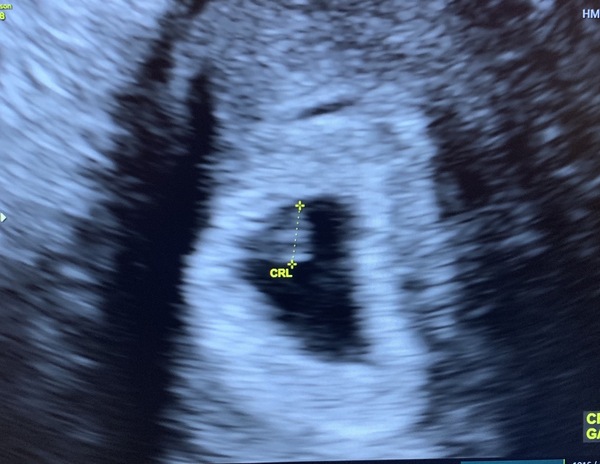

Scan yesterday wasnt good news.

We couldn’t see a heartbeat and it measured at 6+1, not 7+3.

Have to go back in a week but it’s not looking good.